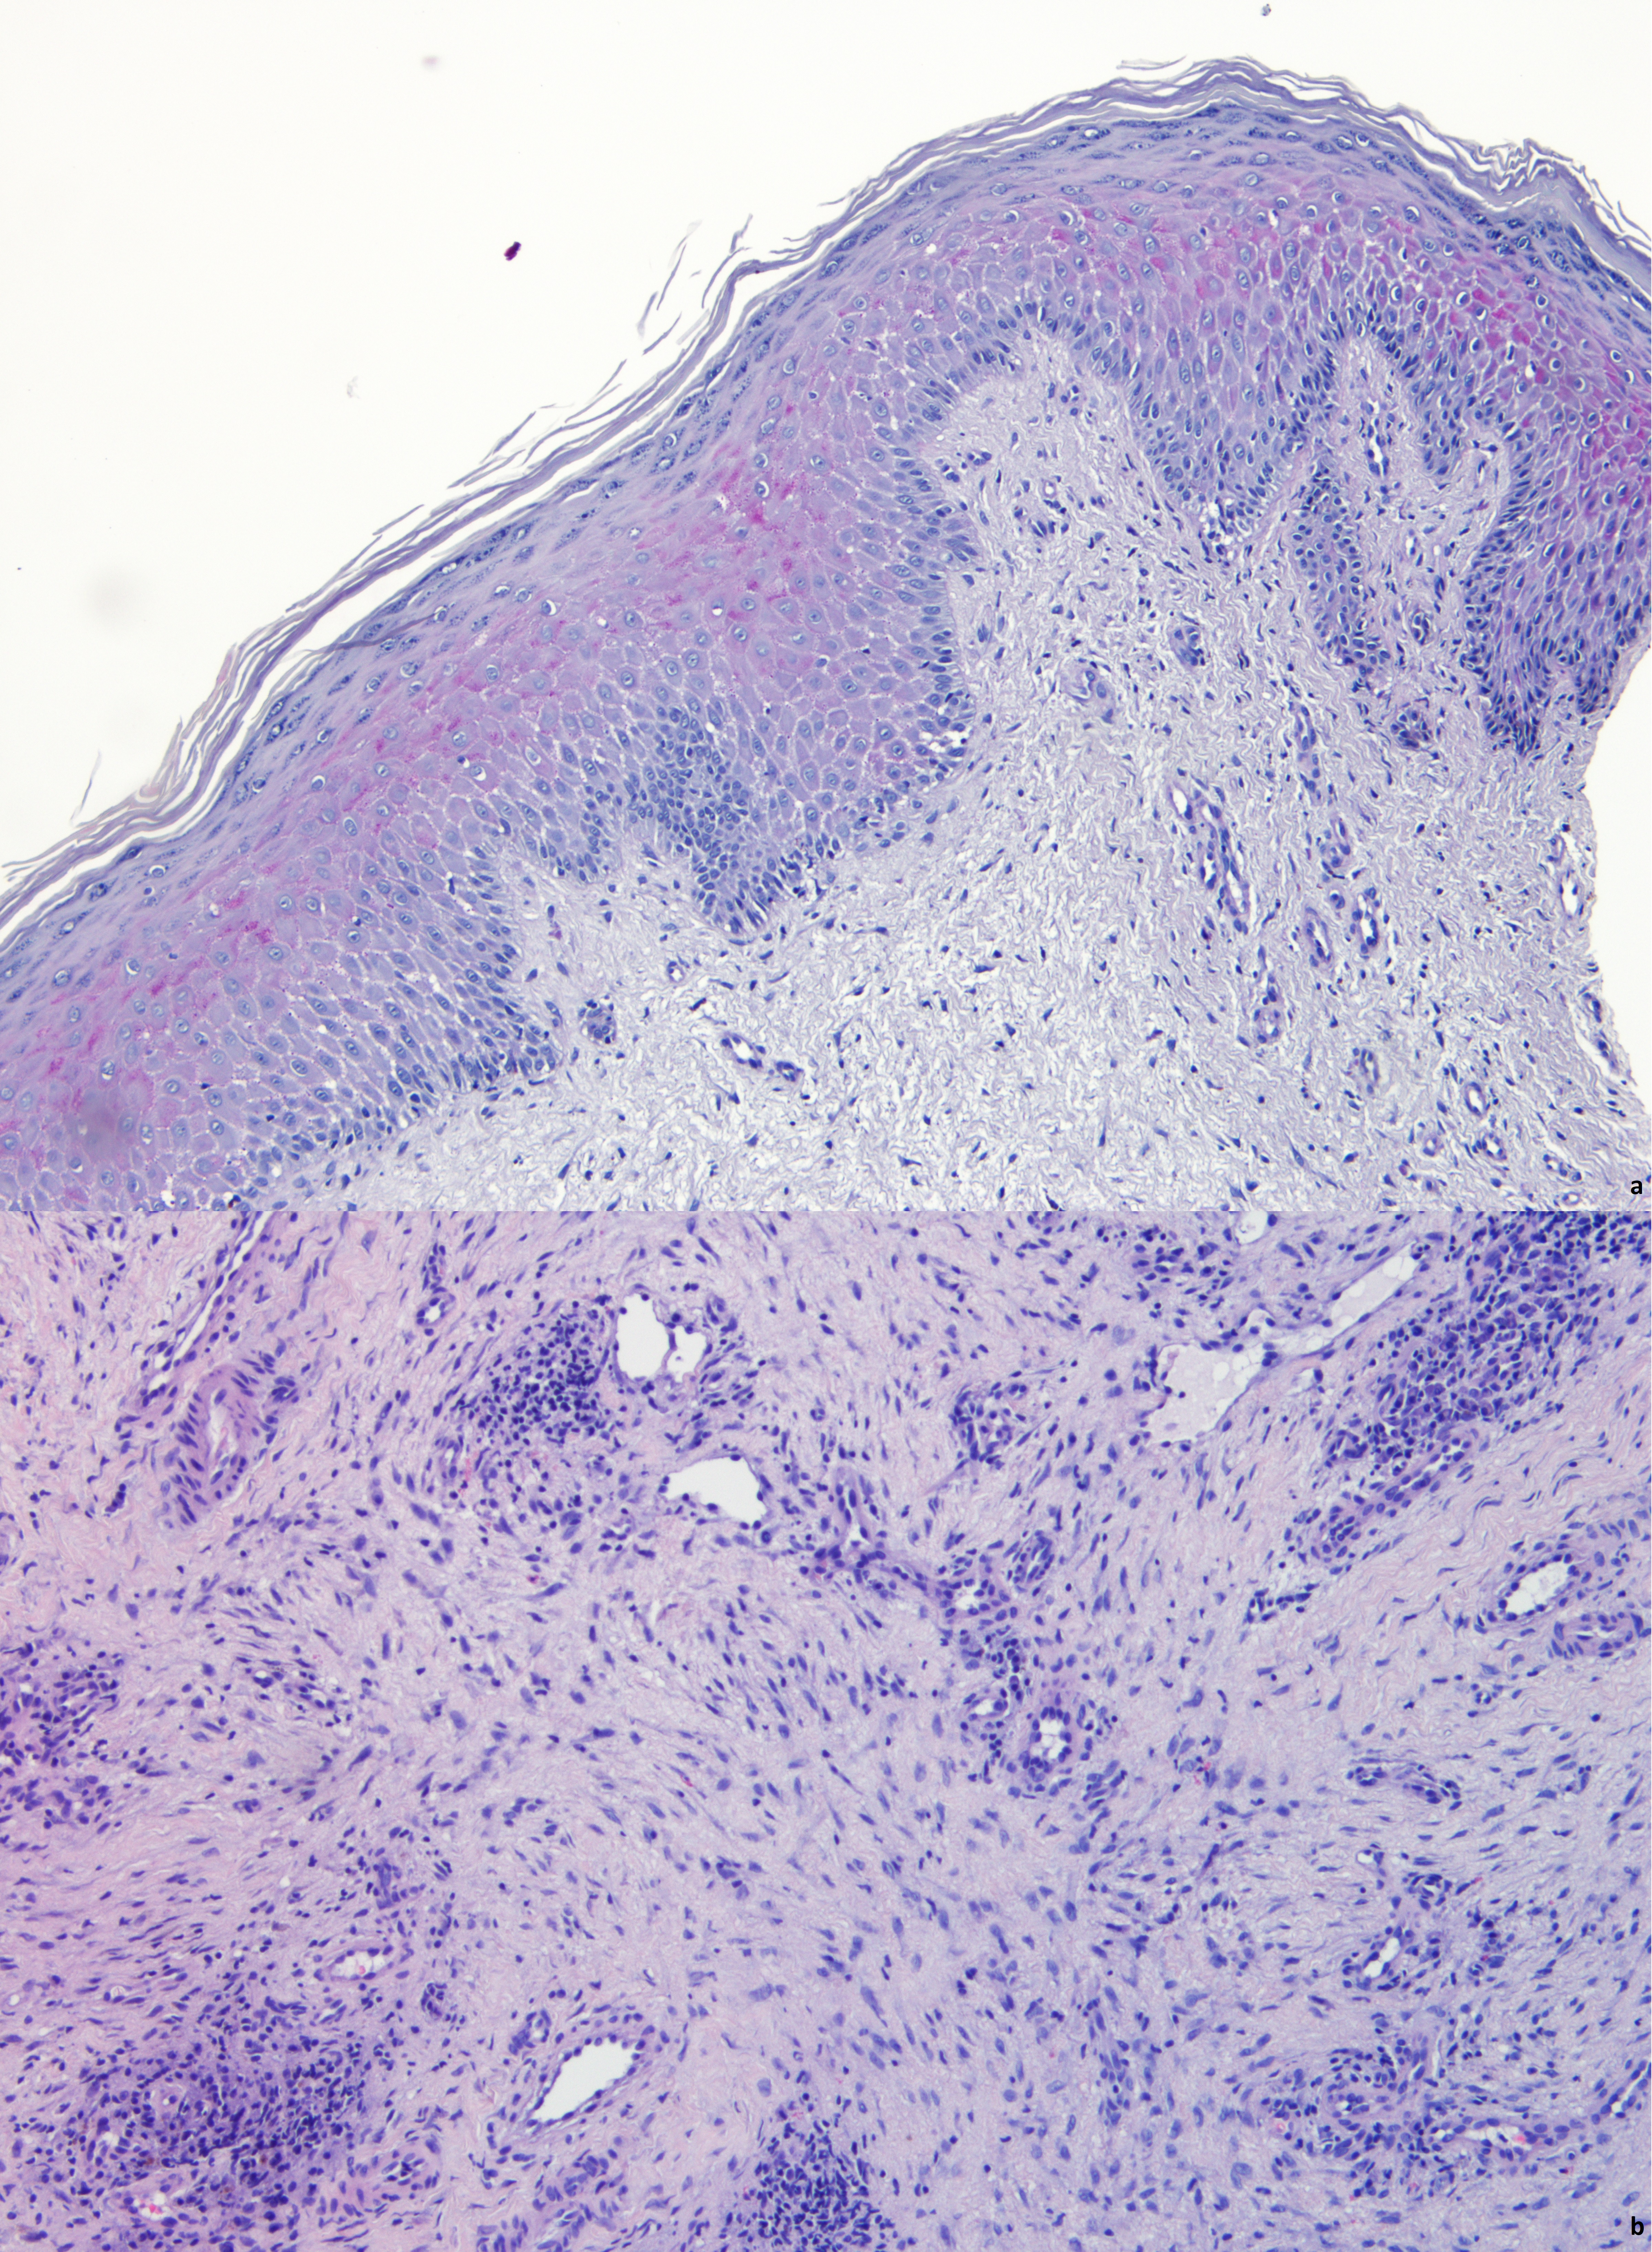

An Exuberant Case of Lymphedema in Young Adults with Morbid Obesity